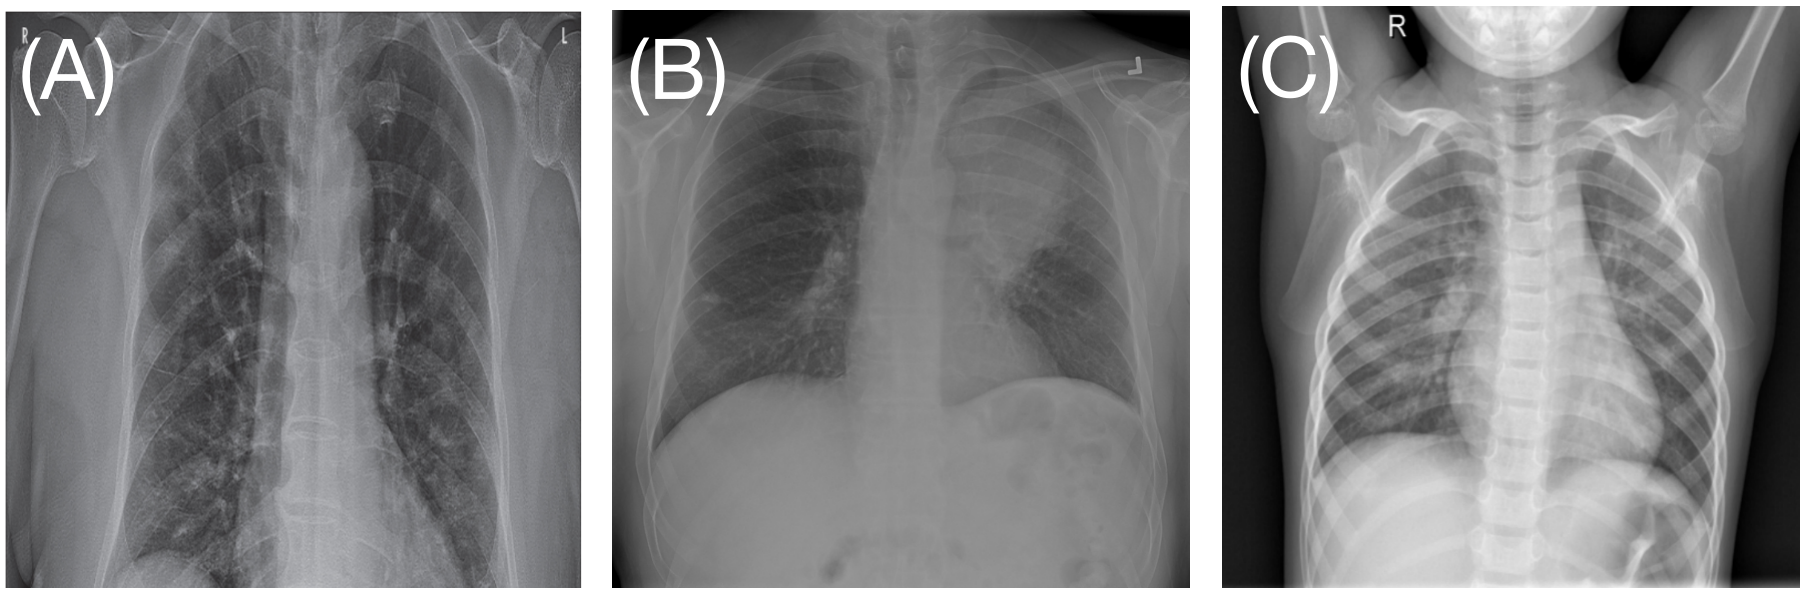

The public COVID-19 patient dataset, COVIDx, was used to evaluate the performance for the task of multi-class classifications. This dataset includes 13,958 2D chest X-ray (CXR) images collected from 13,870 patients, with the diagnosis of three classes of COVID positive, non-COVID pneumonia, and normal cases. Example images of each diagnosis are shown in Figure 3. The raw image size is 1024×1024102410241024\times 1024 pixels. Details of this dataset are shown in Table 1. This dataset shares the common data-related issues in medical image classification tasks. Only a few hundred images are determined as COVID-19 positive. Severe data imbalance exists where the number of COVID-19 images is much smaller than that of non-COVID pneumonia images. In addition, COVID-19 positive cases and non-COVID pneumonia cases have very high visual similarities, which makes an accurate classification of COVID-19 positive cases a challenging task. This dataset is suitable for evaluating the performance of our proposed strategy on addressing the challenges described above.

Figure 3: Example CXR images of (A) COVID-19 positive case, (B) non-COVID-19 pneumonia case and (C) normal healthy case in the COVIDx dataset.